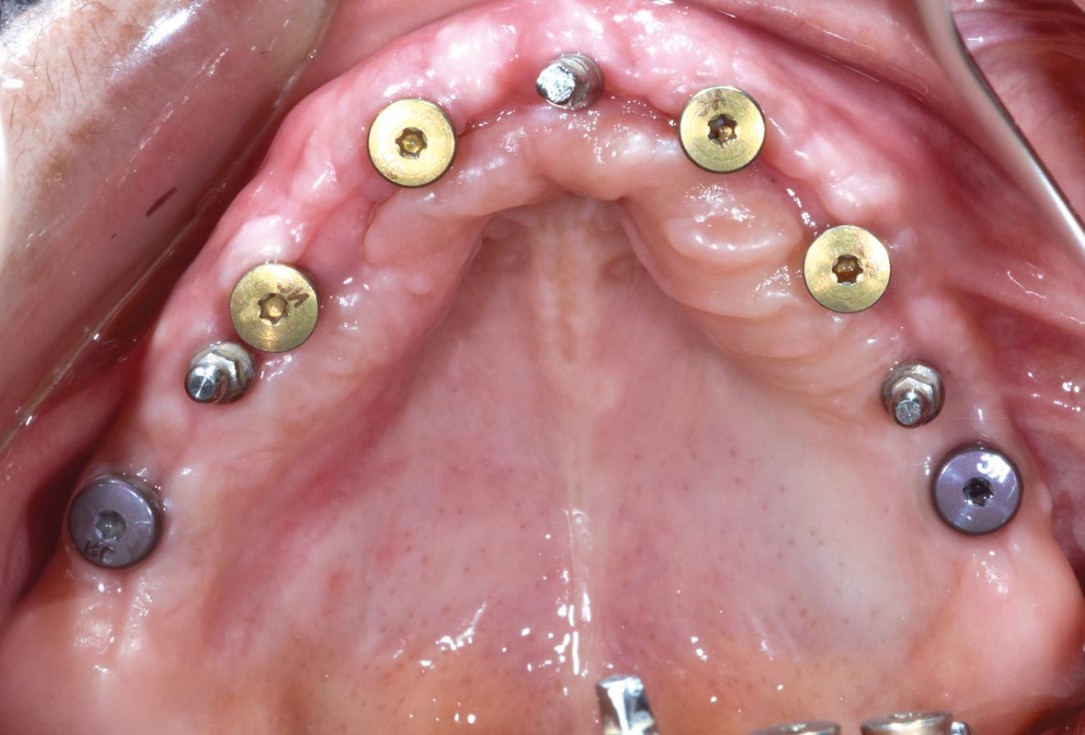

Full arch GBR using cerabone®, maxgraft® and Jason® membrane with simultaneous implantation of 6 Straumann® implants - Dres. A. Signorio and G. Molina